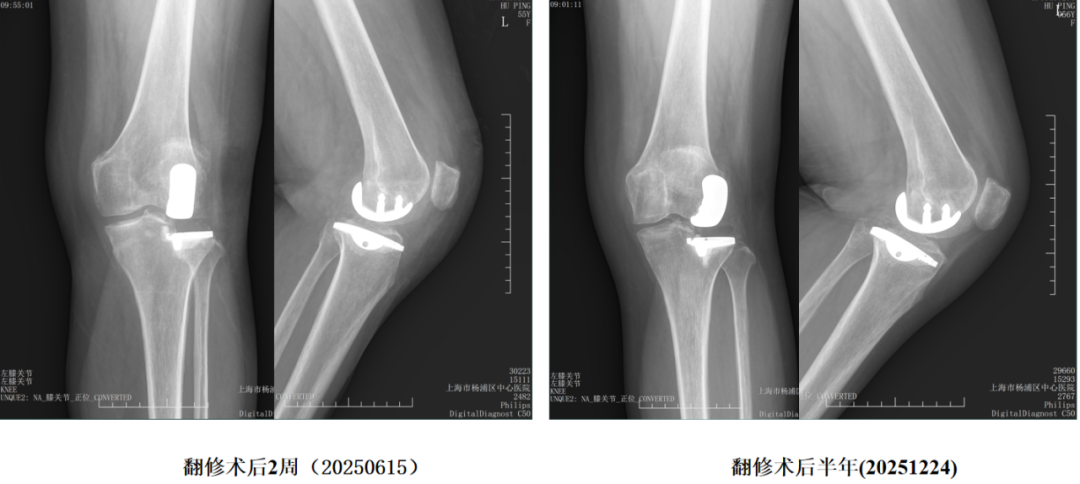

三、胫骨假体下沉翻修

外侧间室OA行LUKA,术后外伤导致胫骨假体塌陷

胫骨假体翻修术(保留股骨假体)

四、胫骨假体过度前倾翻修

LUKA术后胫骨假体过度前倾导致膝关节伸直受限

LUKA术后半年 (20251126)

保留股骨假体胫骨侧翻修

翻修术后 (20251201)